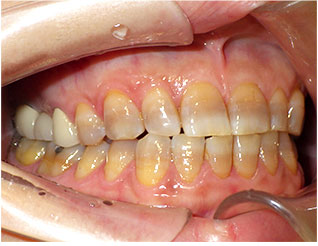

- ブリッジ 症例写真 B-0111フルジルコニア7本 女性モニターの方です。

この方は奥歯に虫歯と歯の欠損がありました。 上下ともブリッジで治療しました。 当院では上下のブリッジ治療を同時進行で行いますので、通院回数が少なく済みます。 また、1回目の治療時に仮歯を入れますので、すぐに見た目が気にならなくなります。 治療回数は5回でした。